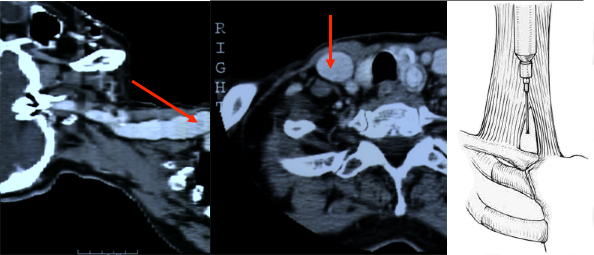

Die in der Anästhesie verbreitete Punktion der distalen Vena jugularis ist komplikationsträchtig und sollte vermieden werden. Normalerweise liegt die Vena jugularis lateral der A. carotis.

Bei der schädelnahen Punktion muß der Kopf nach links gedreht werden, weil sonst das Kinn im Weg ist. Dadurch rotiert die Vene vor die Arterie und das Lumen wird schlitzförmig.

Vor der Einmündung in die Vena anonyma macht die Jugularvene einen Knick von 45 Grad nach dorsal. Diatator, Einführschleuse und Katheter stoßen dort an der Venenvorderwand an und erzeugen Intimaläsionen, die bei 30% der Patienten später zur Thrombose führen.

Darüberhinaus geht der Katheter durch die ganze Breite des Musculus sternocleidomastoideus. Dies führt zu einer rein/raus-Bewegung des Katheters bei jedem Schlucken und jeder Kopfbewegung. Das begünstigt einerseits das Einwandern von Hautkeimen in den Punktionskanal, andererseits werden Fibrinablagerungen auf der Katheteroberfläche an der Punktionsstelle abgestreift. Dadurch kommt es zu einer Akkumulation von Fibrin und thrombotischem Material an der Venenwand und um den Katheter.